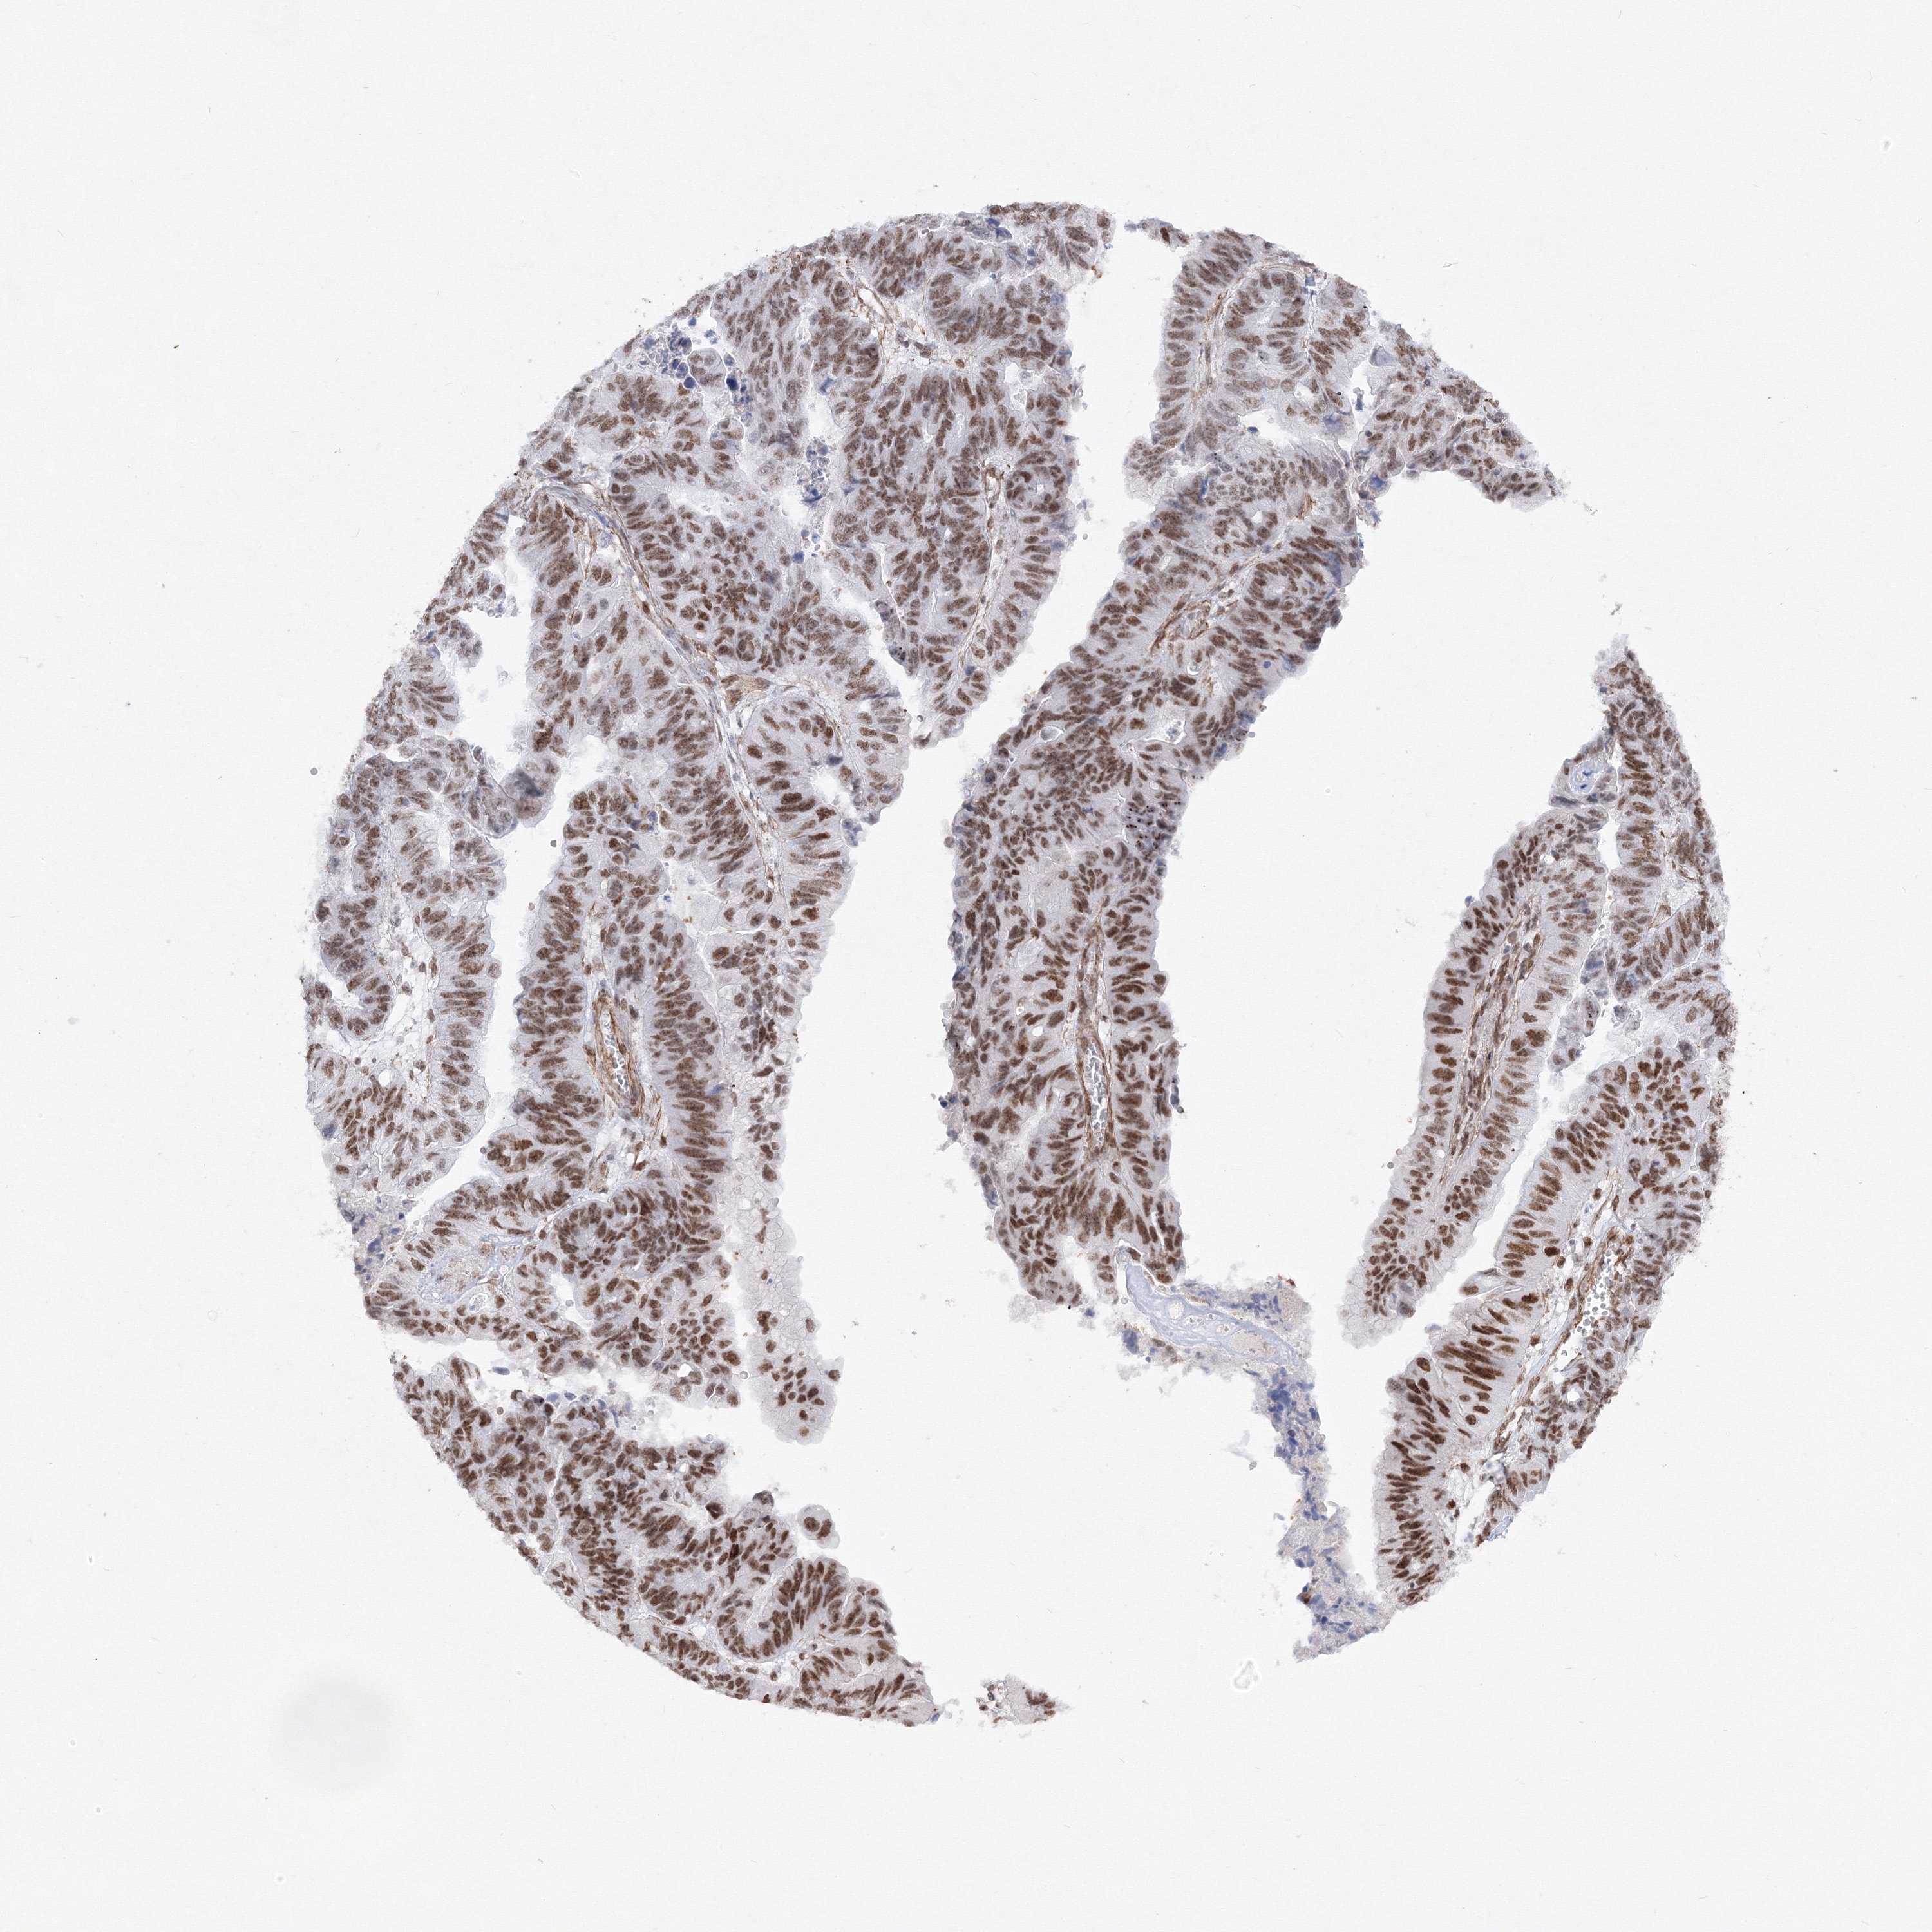

STOMACH CANCER - Protein expressioni

A mouse-over function shows sample information and annotation data. Click on an image to view it in a full screen mode. Samples can be filtered based on level of antibody staining by selecting one or several of the following categories: high, medium, low and not detected. The assay and annotation is described here.

Note that samples used for immunohistochemistry by the Human Protein Atlas do not correspond to samples in the TCGA dataset.

Antibody stainingi

Antibody staining in the annotated cell types in the current human tissue is reported as not detected, low, medium, or high, based on conventional immunohistochemistry profiling in selected tissues. This score is based on the combination of the staining intensity and fraction of stained cells.

Each image is clickable and will lead to virtual microscopy that enables deeper exploration of all samples and also displays staining intensity scores, fraction scores and subcellular localization as well as patient and tissue information for each sample.

Antibody HPA036784

Staining

High

Medium

Low

Not detected

Intensity

Strong

Moderate

Weak

Negative

Quantity

>75%

75%-25%

<25%

None

Location

Nuclear

Cytoplasmic/membranous

Cytoplasmic/membranous,nuclear

Adenocarcinoma, NOS